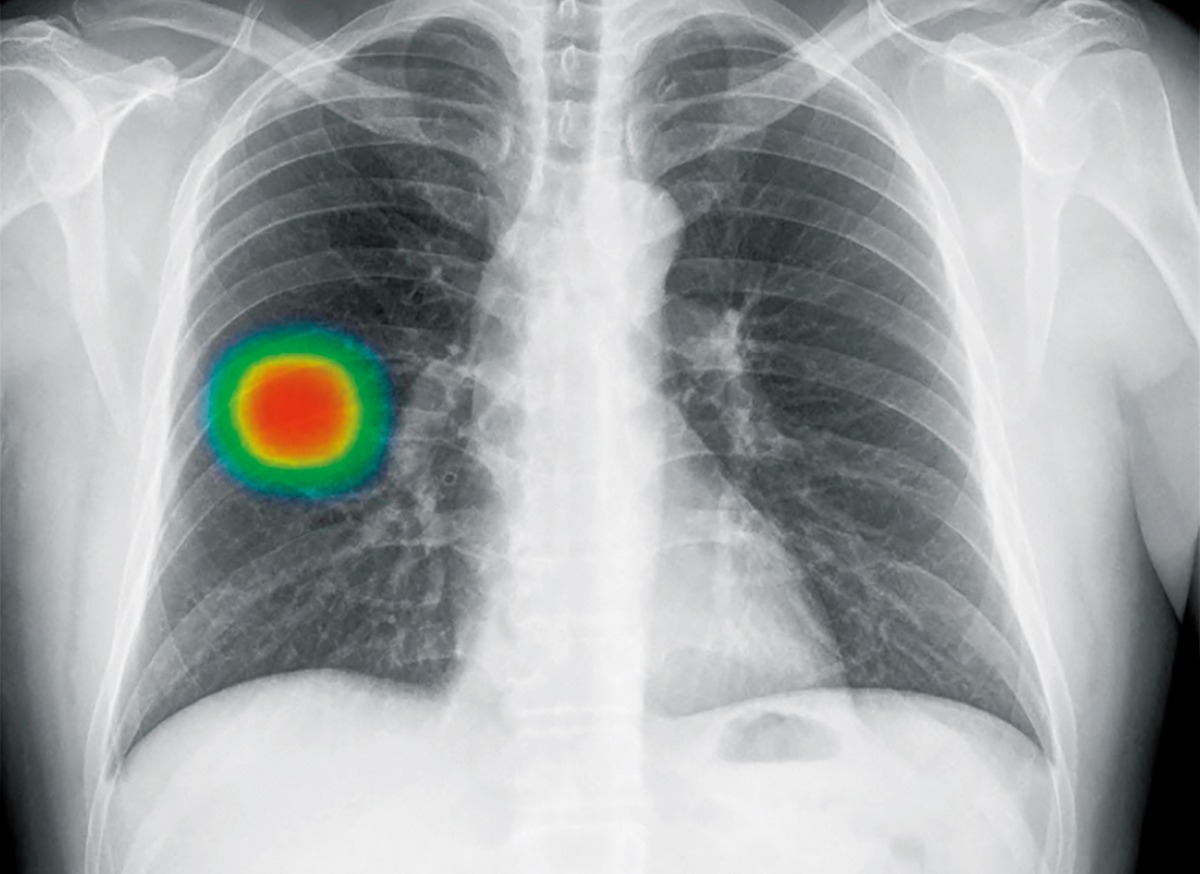

▲先進機器で鮮明に。日常診療を支える胸部レントゲン

同院では最近、レントゲン装置を先進機器へと更新。高画質化に加え、AIによる画像解析を併用することで、病変の見落としを防ぐ体制を整えた。撮影した画像はAIが自動でチェックし、疑わしい部位を色分け表示。最終的な判断は医師が行うが、異常の早期発見につながる大きな武器となっている。

▲AIが異常部位を色で示唆。見落とし防止に貢献

レントゲンは定期健診や不調時の基本検査として多くの患者が利用するだけに、こうした進化は安心感にも直結する。見慣れた検査の裏で進化を続ける設備。その先には、地域の人々がより長く健康に暮らせる未来を見据えたクリニックの姿勢がある。